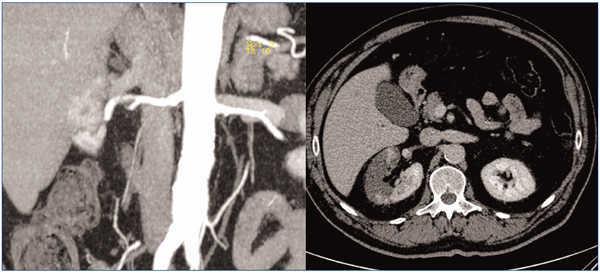

Ante el intenso dolor y la elevación de LDH, se decide solicitar una tomografía computarizada que evidencia un extenso infarto renal derecho con un defecto de repleción en la arteria renal principal, justo proximal a su trifurcación (figura 1).

Figura 1. Diferentes proyecciones del infarto renal derecho en la tomografía computarizada